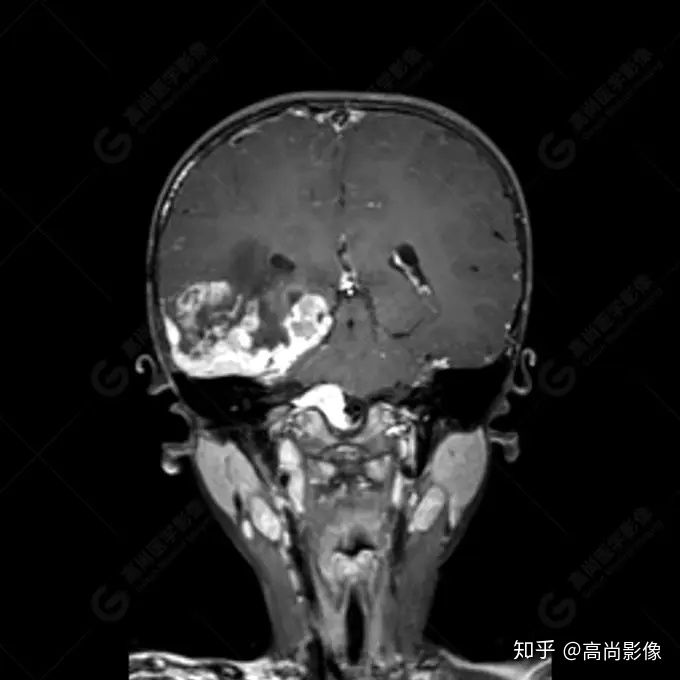

右側(cè)顳葉腫瘤切除術(shù)后(具體不詳):右側(cè)顳部骨質(zhì)不連續(xù)呈術(shù)后改變,右側(cè)顳葉術(shù)區(qū)見片狀長T1長T2信號影,F(xiàn)LAIR呈低信號;術(shù)區(qū)后方右側(cè)顳枕葉見一巨大占位性病變影,邊界欠清,大小約6.2×5.8×4.3cm(前后×左右×上下),信號不均勻,T1WI呈等稍低信號間雜少許高信號,T2WI呈高稍低混雜信號,DWI示部分病灶彌散受限,相應(yīng)ADC圖減低,磁敏感序列見部分呈極低信號,增強(qiáng)掃描可見明顯不均勻強(qiáng)化,鄰近硬腦膜及小腦幕增厚并明顯強(qiáng)化;另延髓右前方及右側(cè)橋小腦角區(qū)見一不規(guī)則形異常信號影,大小約3.2×1.3×3.7cm(左右×前后×上下),呈長T1稍長T2信號,F(xiàn)LAIR呈等信號,DWI未見受限,增強(qiáng)后明顯均勻強(qiáng)化,鄰近腦膜明顯強(qiáng)化。鄰近腦實質(zhì)及右側(cè)顳角明顯受壓;左側(cè)大腦半球未見局灶性信號異常,中線結(jié)構(gòu)稍左移。

右側(cè)顳葉腫瘤切除術(shù)后:現(xiàn)術(shù)區(qū)后方右側(cè)顳枕葉及延髓右前方占位,右側(cè)顳枕部硬腦膜及小腦幕明顯強(qiáng)化,結(jié)合既往影像資料,考慮為胚胎源性惡性腫瘤,如非典型畸胎樣/橫紋肌樣瘤(AT/RT)或原始神經(jīng)外胚層腫瘤(PNET)。

術(shù)后隨訪病理結(jié)果:非典型畸胎樣/橫紋肌樣瘤。

非典型畸胎樣/橫紋肌樣瘤(AT/RT) 是一種高度惡性中樞神經(jīng)系統(tǒng)腫瘤,臨床罕見,臨床表現(xiàn)無特異性,好發(fā)于 5 歲以下兒童,尤以 3 歲以下多見,在兒童原發(fā)性中樞神經(jīng)系統(tǒng)(CNS)腫瘤中占 1%~3%。該腫瘤體積一般較大,幕上大于幕下,有明顯的占位效應(yīng)。該腫瘤成分復(fù)雜,囊變、出血、壞死常見。因此 AT/RT信號混雜,囊性部分呈 T1WI低、T2WI高信號,增強(qiáng)后不強(qiáng)化;若瘤體出血,囊內(nèi)可見T1WI稍高信號、T2WI低信號,實性部分在 T1WI上呈混雜等、低信號,在T2WI 及 T2-FLAIR上呈混雜等高信號,增強(qiáng)掃描后大部分呈環(huán)形條帶樣明顯強(qiáng)化,中心壞死區(qū)不強(qiáng)化。另外,該腫瘤實性成分在DWI上呈高信號,說明腫瘤細(xì)胞核密集,水分子擴(kuò)散明顯受限,提示該腫瘤惡性程度高,容易復(fù)發(fā)及轉(zhuǎn)移。